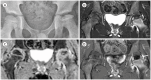

Developmental dysplasia of the hip is a condition characterized by hip joint instability due to acetabular dysplasia in infancy, necessitating precise ultrasound examination. Legg-Calvé-Perthes disease is caused by a temporary disruption in blood flow to the femoral head during childhood, progressing through avascular, fragmentation, re-ossification, and residual stages. Slipped capital femoral epiphysis is a condition where the femoral head shifts medially along the epiphyseal line during adolescence due to stress, such as weight-bearing. Differentiating between transient hip synovitis and septic arthritis may require joint fluid aspiration. Osteomyelitis can be associated with soft tissue edema and osteolysis. When multiple lesions are present, it is essential to distinguish between Langerhans cell histiocytosis and metastatic neuroblastoma. This review will introduce imaging techniques and typical findings for these conditions.